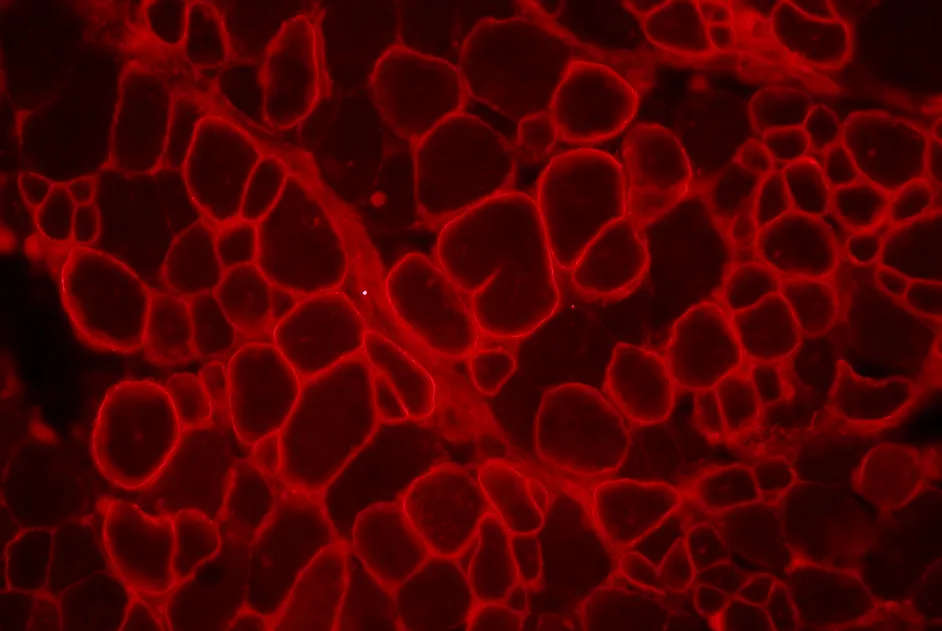

Testée dans plusieurs modèles animaux et cellulaires de DM1, la chloroquine améliore l’atteinte musculaire et réduit les signes pathologiques au niveau cellulaire.